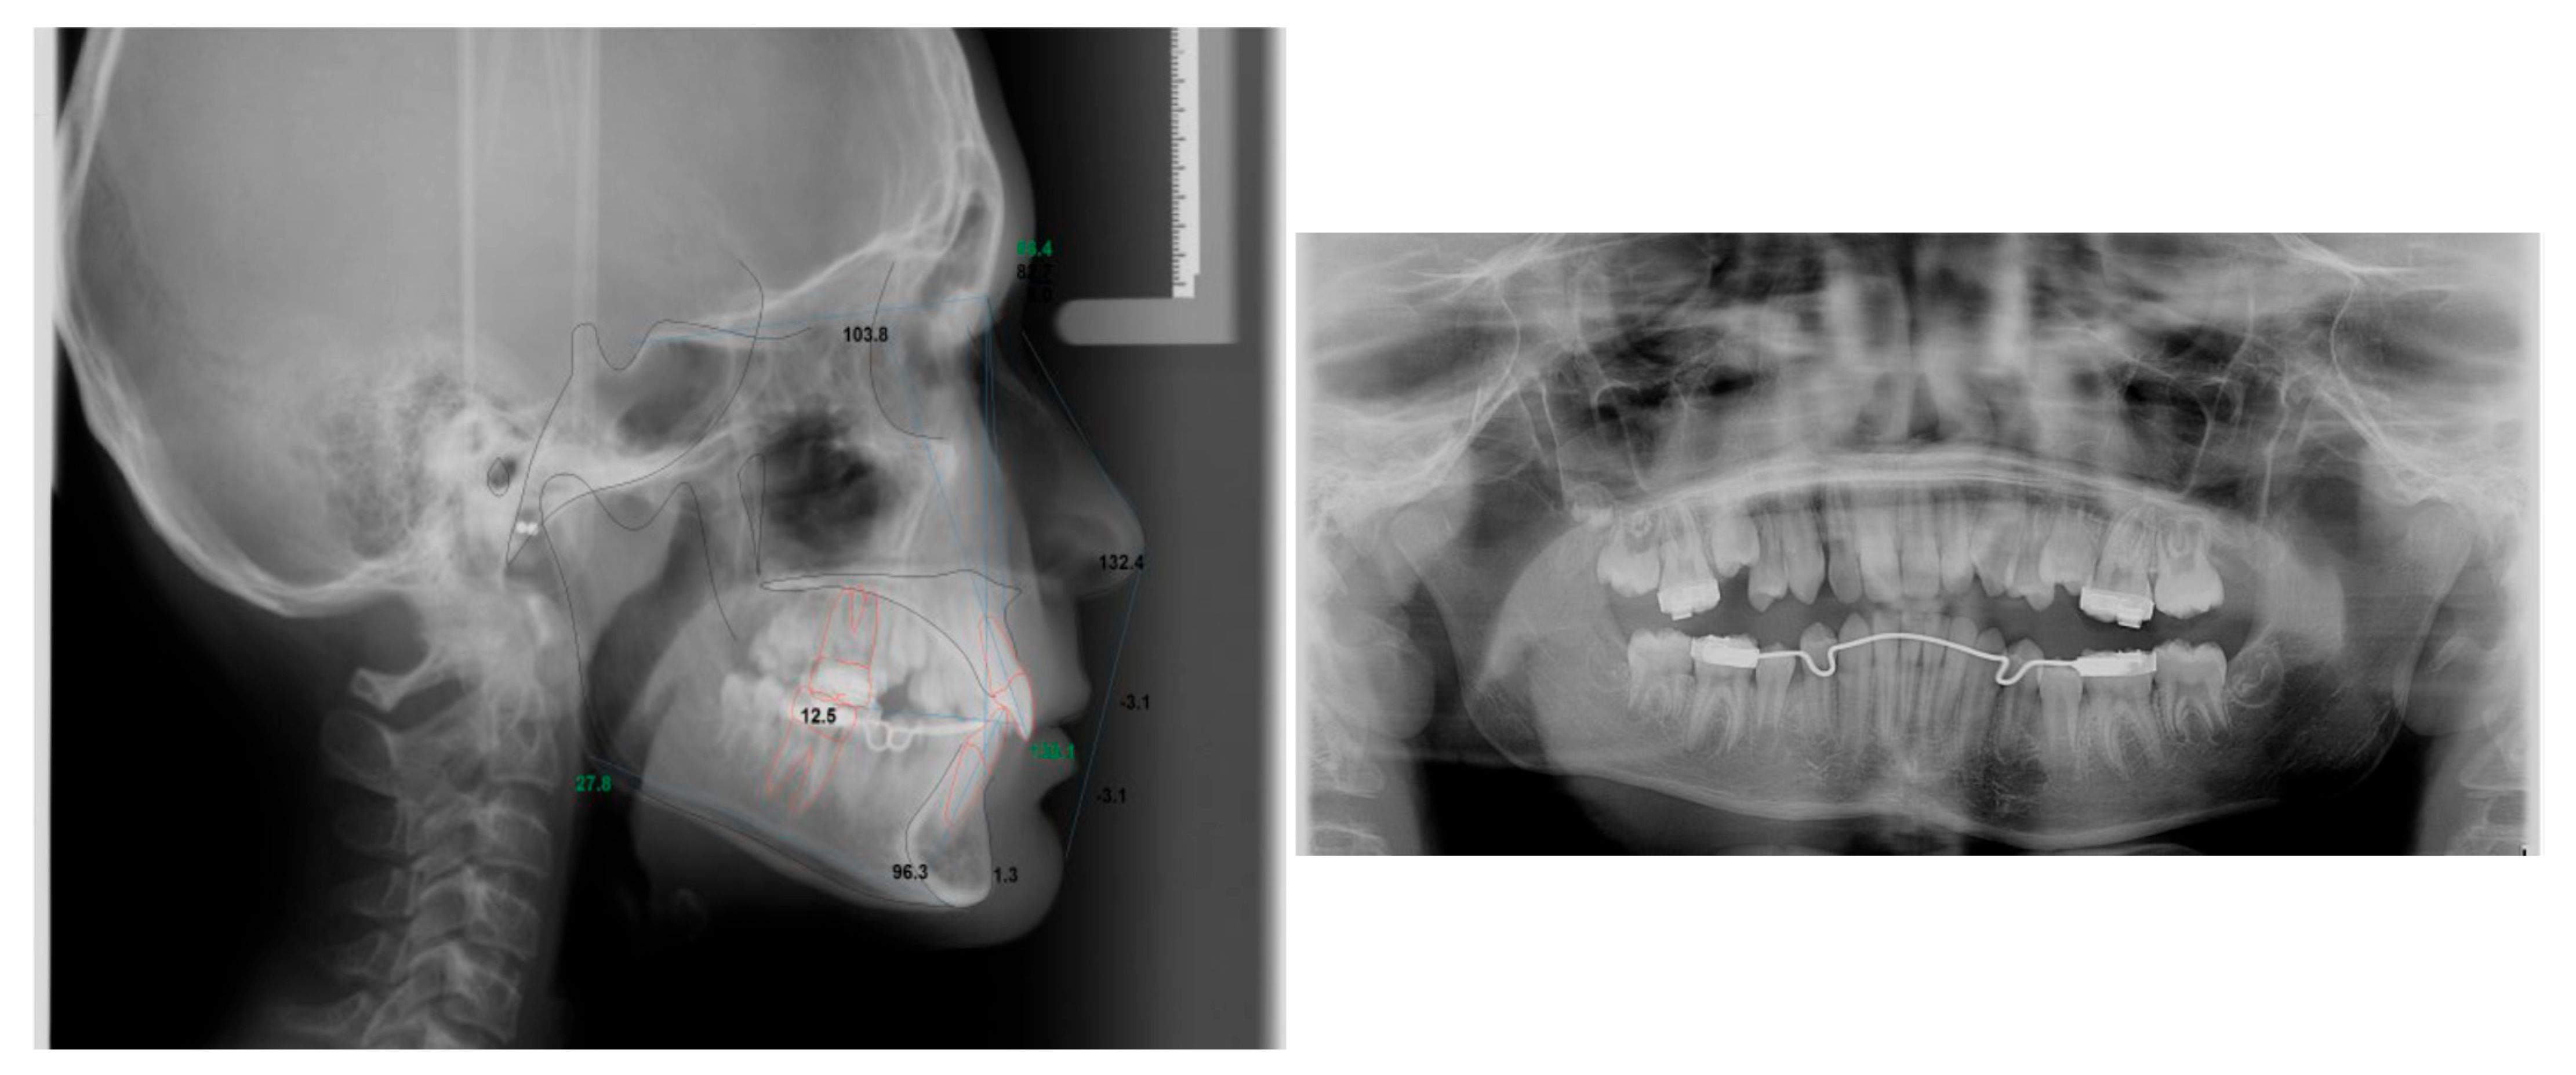

Figure A2.

Full records of the patient.

Table A2.

Demographic data and cephalometric analysis of the case.

| Age | 11 years | Over Jet = 3 mm |

| Sex | Male | Over bite = 5 mm |

| Breathing | Nasal | |

| Cephalometric analysis | ||

| Normal values | Patient values | |

| SNA | 80 | 86.4° |

| SNB | 78 | 82.7° |

| ANB | 2 | +3.7° |

| FMA | 21 | 23° |

| SN-GoGn | 32 | 27.8° |

| Maxillary incisor to SN | 105 | 103.8° |

| Mandibular incisor to GoGn | 95 | 96.3° |

| Soft tissue | ||

| Lower lip to E-plane | –2.0 mm | −3.1 mm |

| Upper lip to E-plane | –1.6 mm | −3.1 mm |

Appendix A.3. Case 3